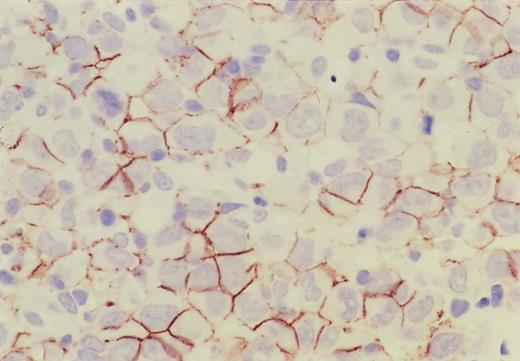

The results are summarized in Table2 and categorized according to ALK-positive and ALK-negative subgroups. Immunohistochemical profile of a CD56-positive case is shown in Figure1. All cases but 1 were positive for CD30, and CD56 was positive in 13 of 81 cases (18%) of the ALK-positive group and in 12 of 59 cases (20%) of the ALK-negative group, so that the incidence of expression was almost the same. None of the ALK-positive group showed any expression of CD15, BCL-2, or EBV, but most of them were positive for epithelial membrane antigen (EMA). On the other hand, the expression of these markers was somewhat heterogeneous for the ALK-negative group, resulting in a statistically significant difference between these 2 groups. In HD-like ALCL, the expression of CD15 was found in 4 out of 10, the expression of EMA in 7 out of 9, and the presence of EBV in 2 out of 10 cases. Of the 4 CD15+ cases, 3 were also positive for EMA; the remaining case was not examined for EMA. Only one case showed simultaneous expression of CD15 and EBV, but the neoplastic cells were also positive for EMA and CD45RO. The expression of cytotoxic molecules (TIA-1 and granzyme B) was significantly higher in the ALK-positive group (P < .0001 and P = .007, respectively).

Immunohistochemistry of CD56 in ALCL.

CD56 is expressed on the cell surface membrane of the lymphoma cells, and its expression is more intense on the adjacent membrane of neighboring cells.